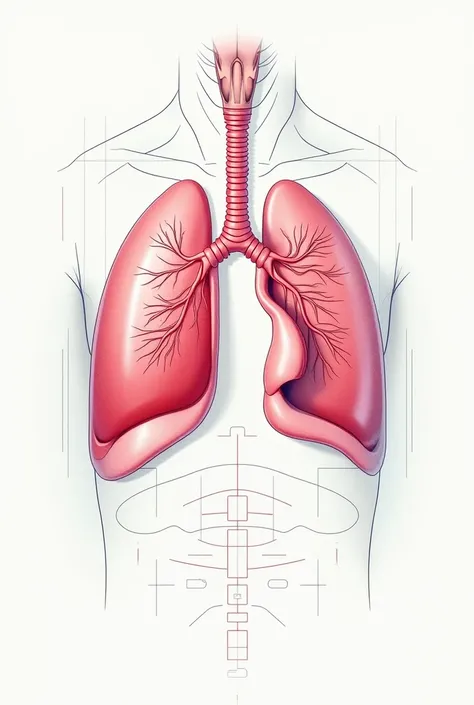

Make a folder about bacterial pneumonia

Make a folder about bacterial pneumonia

Make a folder about bacterial pneumonia